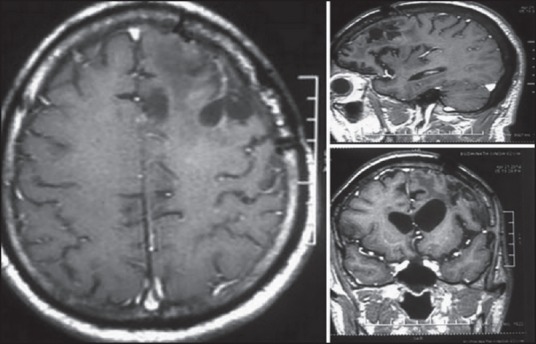

Figure 1.

Postoperative MRI scan showing tumor excision

A 60-year-old male patient presented with slurring of speech and progressive weakness of the right side of the body since 1 month in June 2011. Magnetic resonance imaging (MRI) of the brain was suggestive of a large left frontal irregular, heterogeneously enhancing lesion. He underwent left frontoparietal craniotomy and gross total tumor excision [Figure 1]. Histopathology was suggestive of GBM, World Health Organization (WHO) grade IV. The patient then underwent external beam radiotherapy (EBRT) in a dose of 59.4 Gy in 33 fractions for 6 weeks with chemotherapy (Temozolamide capsule 100 mg daily) with an uneventful course. He remained stable, and postoperative MRIs during follow-up were not suggestive of residual/recurrent disease.